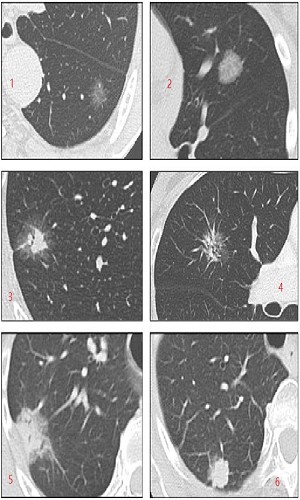

胸部CT检查结论中常出现磨玻璃结节,肺部结节按密度高低分为纯磨玻璃结节、混合磨玻璃结节、实性结节。总体来看,纯磨玻璃结节、混合性磨玻璃结节、实性结节的恶性概率分别约为18%、63%、7%。

1、2为纯磨玻璃结节;3、4、5为混合性磨玻璃结节;6为实性结节